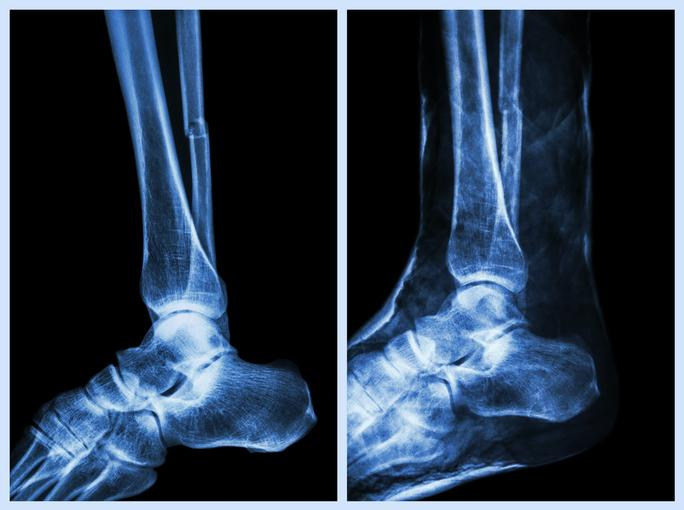

자신이 족저근막염을 앓고 있는지에 대한 여부를 알아보기 위해, 우선 족저근막염정형외과 방문이 요망된다. 이후 의사와의 상담과 진찰을 거친 다음 X레이 검사, MRI, CT촬영을 하거나 근전도 검사를 실시한다. 발뒤꿈치통증이 족저근막염 때문인지, 혹은 점액낭염이나 시버병, 전신 염증성 질환에 의한 것인지 알아보기 위하여 추가적인 검사를 진행할 수도 있다.